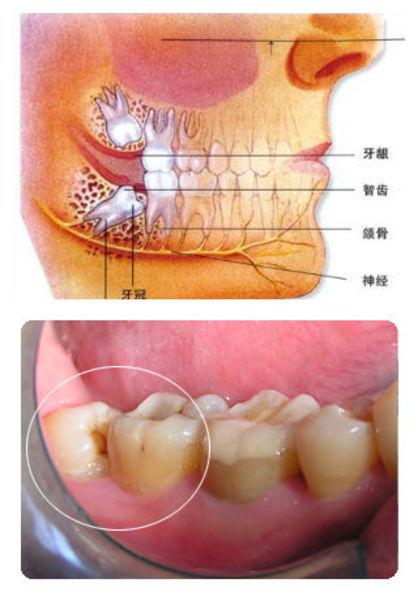

智齿正常位置

智齿位置

智齿位置图

智齿的位置图片

智齿长在哪里